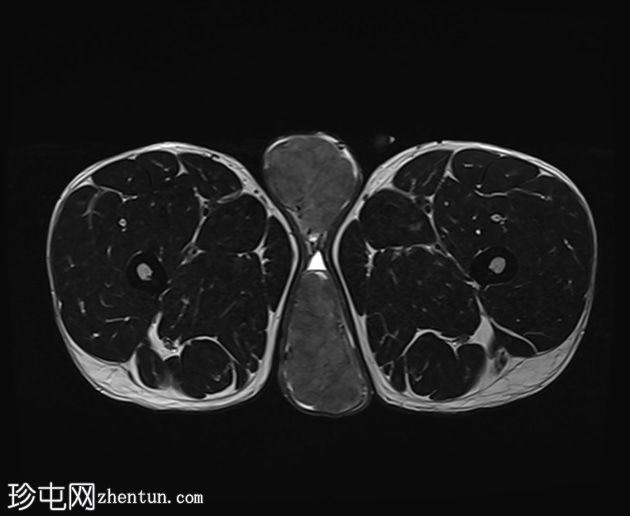

轴位

STIR序列

阴囊内睾丸增大,T1加权像上可见分叶状软组织病变,呈中高信号,T2加权像上呈低信号。

轻度双侧鞘膜积液。

本病例表现为双侧睾丸肿胀,影像学特征符合睾丸肾上腺残余肿瘤的典型表现,即T1加权像上呈双侧中高信号,T2加权像上呈低信号。